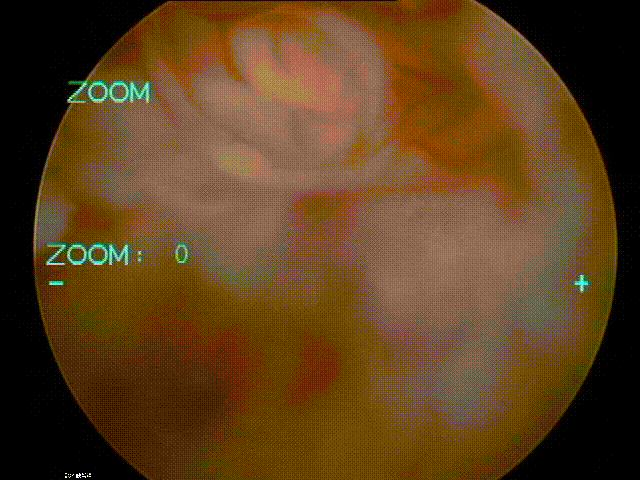

九、类脊髓高压综合征

病例

女,51岁。

主诉:腰疼伴左下肢疼痛麻木4个月。

既往史:椎间孔镜下椎间盘切除术(L4-5)。

术前

术中:术中硬膜破裂,灌洗液压力30mmHg,硬膜破裂后1小时出现血压升高,心率加快,手术持续2小时。

术后:延迟苏醒,拔管困难,转ICU,6小时候拔管神志恢复正常。

术后

思考与建议:

警惕硬膜损伤

全麻下早期表现:血压升高,心率加快

尽快结束手术或中转开放手术

有条件情况下给予硬膜修补

多数患者预后良好